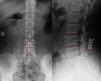

Material y métodoSe estudiaron 71 casos de hernia discal L4-L5 intervenidos en nuestro hospital mediante discectomía y colocación de espaciador interespinoso. Se utilizaron técnicas de morfometría geométrica: análisis procrustes y componentes principales. Se comparan los resultados morfológicos con la lordotización, distracción quirúrgica, así como con variables clínicas (índice de Herron y Turner).

ResultadosSe identificó significativa variabilidad morfológica tanto en forma de traslación cráneo-caudal como rotación horaria-antihoraria en la posición del implante. Esta variación no se correlacionó con el resultado clínico, pero sí con variables anatómicas (grado de lordosis), y con aspectos quirúrgicos (distracción adicional del implante). Se detectó, igualmente, un emplazamiento ligeramente diferente en los casos con recidiva.

Materials and methodsWe performed a retrospective study on X-ray films from 71 patients suffering from disc herniation in L4-L5 who underwent surgery in our hospital, consisting of: microdiscectomy and biomed interspinous spacer implantation. The geomorphometric techniques used to analyse the data were procrustes superimposition and principal components analysis. We compared the clinical results (using the Herron and Turner scale), segmental lordosis and surgical distraction with the geomorphometric parameters.

ResultsSignificant morphological variability was found in the implant position showing cephalo-caudal translation and clockwise-counterclockwise rotations. This variability did not correlate with clinical results. A relationship with anatomical features (lordosis) and additional surgical distraction was identified. A different morphology of implant-segment configuration was identified in cases with recurrence of disc herniation.